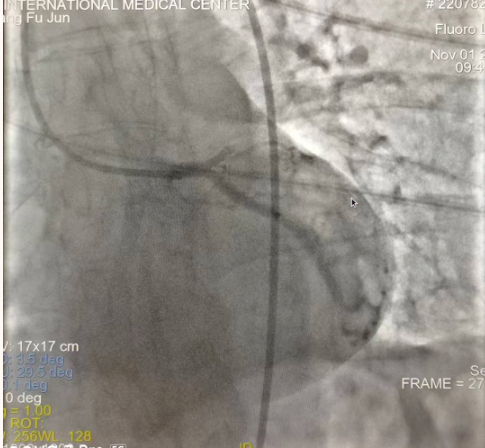

閉塞的血管再通時間取決于急救時長、轉(zhuǎn)運時長和治療時長,在前兩方面,醫(yī)院已為患者爭取了最短時間?;颊呒覍龠h在陜北,雖然已在趕來的路上,但最快抵達西安也要3小時,在與患者家屬電話溝通同意急診手術(shù)后,醫(yī)療總值班代家屬簽字,康曉軍在請示心臟病醫(yī)院王海昌院長及心臟內(nèi)科CCU尚福軍主任后,積極進行術(shù)前準備。在沒有家屬陪同、沒有交費、沒有辦入院手續(xù)的情況下,患者經(jīng)胸痛中心綠色通道被送往心臟冠脈介入手術(shù)室,打通了完全閉塞的心臟前降支近段血管。